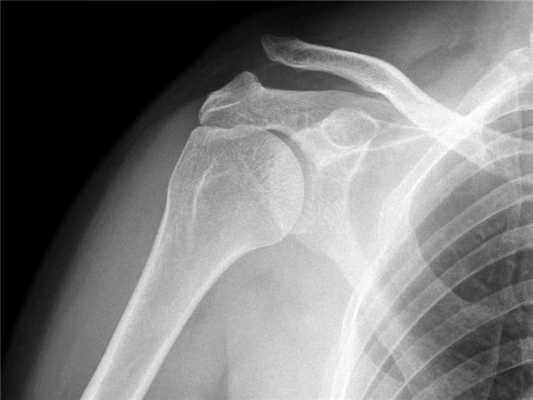

В травматологическое отделение ГКБ им. С.П.Боткина поступил пациент А.А.Ф., 37 лет (и.б. No1068) с травматическим полным вывихом акромиального конца правой ключицы шестидневной давности (рис. 1). Предоперационное обследование заняло двое суток.

Ранний послеоперационный период протекал без осложнений, рана зажила первичным натяжением, швы удалены в положенные сроки. Больной соблюдал предписанный ему режим иммобилизации ортезом типа Дезо. По прошествии 4-х недель с момента операции произведено удаление спиц и выполнена контрольная ренгенография (рис. 3).

Поставить диагноз можно на основании рентгеновского снимка.

Для постановки диагноза и для определения степени повреждения акромиально-ключичного сочленения наиболее информативным методом исследования является рентген.

На рентгене при первой степени разрыва акромиально-ключичного сочленения будет видно расхождение между ключицей и акромионом.

При второй степени мы видим выступание ключицы над акромионом на расстояние не более половины ее диаметра.

При третьей степени ключица выступает над лопаткой на полный свой диаметр и даже более того.